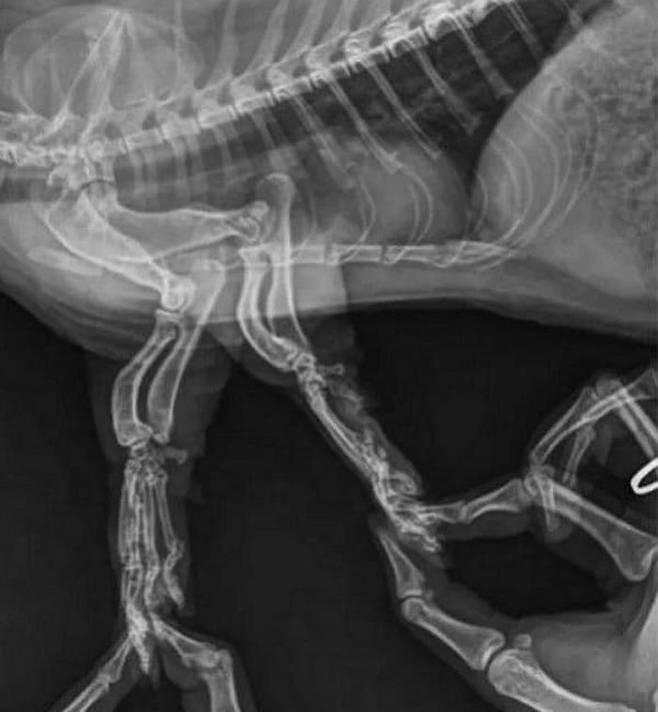

그렇다면 사진은 잘 촬영이 되었을까. 공개된 사진 속을 보면 먼치킨 고양이의 다리를 붙잡고 있는 집사 손가락까지 찍혀 있음을 확인할 수 있었죠.

보면 볼수록 너무 귀여운 먼치킨 고양이의 엑스레이 사진 찍는 과정 아닌가요. 다행히도 먼치킨 고양이의 엑스레이 사진 촬영 결말은 무사히 끝났습니다.

한편 사진을 접한 누리꾼들은 "이렇게 귀여울 수가", "저기 집사 손가락 찍힌 것 보이네", "사진 찍기 보통 힘든 일이 아닐 듯", "이게 고양이 매력이지" 등의 다양한 반응을 보였습니다.